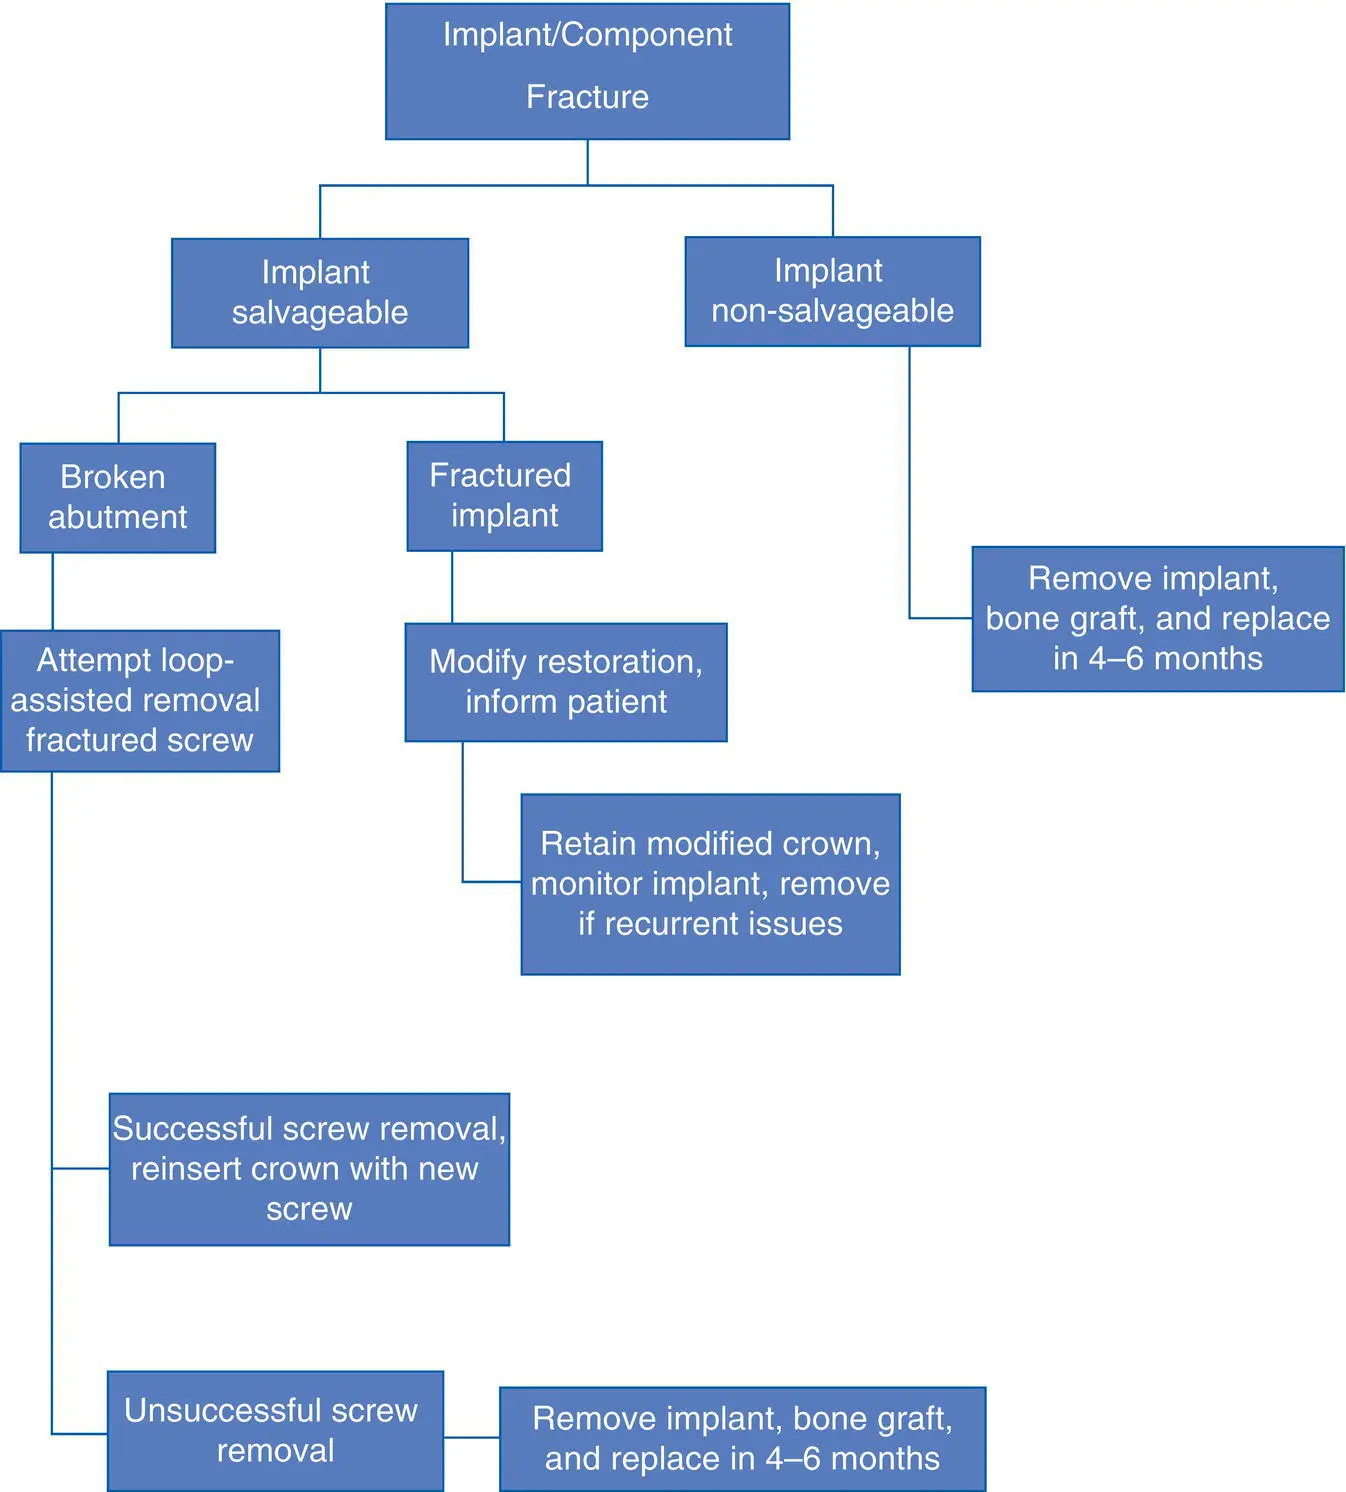

Algorithm 3.8: Fractured Implants and Components